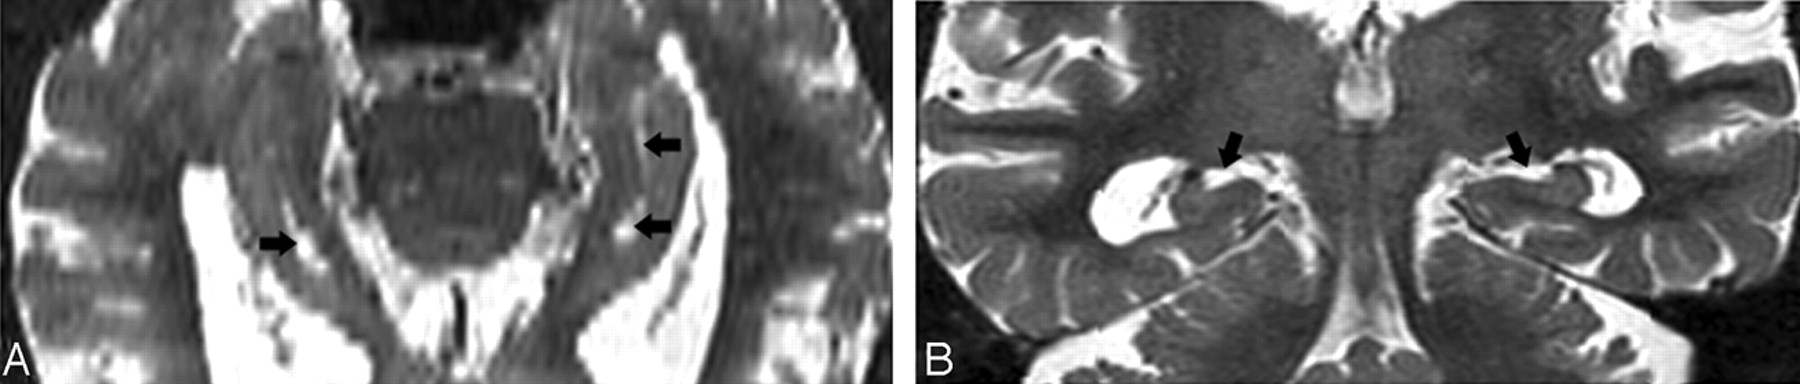

T2 short-τ inversion recovery (STIR) MR coronal image obtained from a 74-year-old male normal control (NC) patient. A, Arrowhead shows a small hippocampal sulcus residual cavity (HSC); arrow shows perihippocampal fissures (PHF) (uncal sulcus). B, 3-year follow-up scan. Comparing A and B, there is progressive dilation of the uncal sulcus (arrow), but no obvious change in the size of the HSC (arrowhead).

T2 short-τ inversion recovery (STIR) MR coronal image was obtained from a 73-year-old male normal control (NC) patient. Arrows show a dilated uncal sulcus and no hippocampal sulcus residual cavity (HSC). B, 3-year follow-up.

T2 short-τ inversion recovery (STIR) MR image was obtained from a 66-year-old female normal control (NC) patient.

A, Axial plane, arrowheads show the hippocampal sulcus residual cavity (HSC) and arrow shows the uncal sulcus. We can best differentiate them on the coronal plane.

Image obtained from a 90-year-old female normal control (NC) patient. Axial (A) and coronal (B) T2 short-τ inversion recovery (STIR) MR image show the perihippocampal fissures (PHF) (black arrows). This is also best seen along the coronal plane (B).

In the coronal plane, the differentiation of a HSC in the presence of a dilated uncal sulcus is challenging. As seen in Figs 4A and 5A, these CSF structures look very similar. They can be differentiated by identifying the medial to lateral course of the uncal sulcus through its continuation with the ambient cistern. This relationship is clearly seen in a 3-year follow-up, when the uncal sulcus, but not the HSC, changed over time (Figs 4B and 5B). In the axial plane, the differentiation of a HSC from the PHF and from uncal sulcus can be difficult (Figs 6A and 7A). Comparing them, the HSC is again the more lateral and distributed along the vestigial primary hippocampal sulcus. We conclude that the coronal plane (Figs 6B and 7B) is most helpful for distinguishing between them.

PHF and the uncal sulcus communicate with the ambient cistern if tracked across sections. Viewing both coronal and axial planes is helpful in challenging cases.